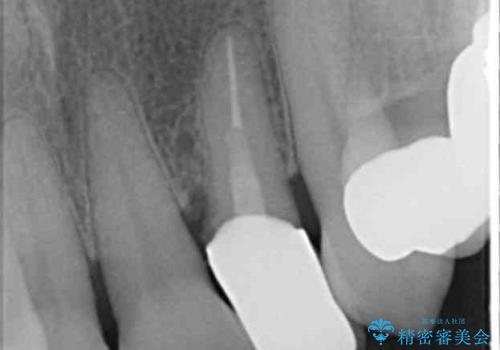

- 下の前歯(左下2)と奥歯の動揺がひどくなってきたことを主訴に来院された患者様です。

精査したところ、前歯の咬み合わせが反対になっていること、下の奥歯(下顎両側67)が4本欠損していることから動揺が生じていました。

入れ歯も抵抗があるとのことから、相談を重ね、今の状態では保存不可能な下の前歯(左下2)を抜去し、ブリッジや連結補綴により動揺を抑えることにしました。

また、咬み合わせが反対になっている上の前歯(左上2)も補綴で形を変えることにより、咬合を改善しました。

- ¥1,110,000 (根管治療×1本、土台×2本、仮歯×9本、クラウン×9本)費用は治療当時の料金となります